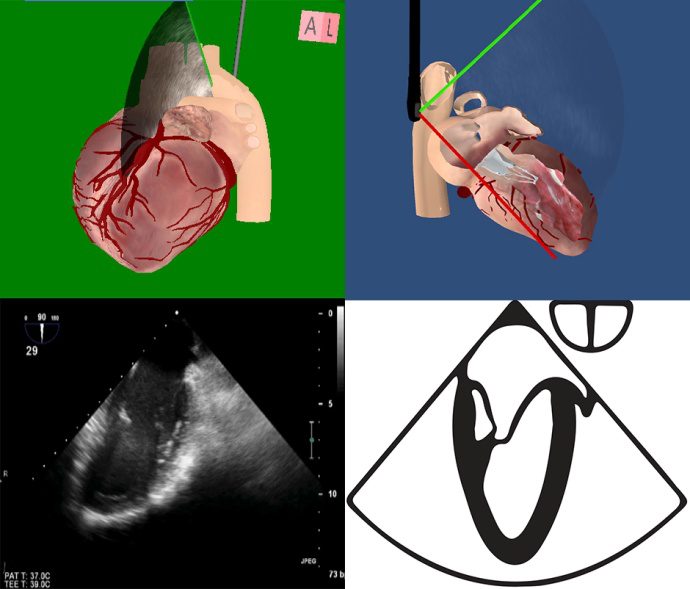

左室长轴 (ME LAX) TEE-Focus基本切面

120°~160° |

|

在左心2腔切面的基础上,面对心脏逆时针旋转切面30°

显示左心房、二尖瓣、左心室流入道;左心室流出道、主动脉瓣、升主动脉。

标准切面不显示二尖瓣下乳头肌 |

1.左心室长轴切面(图5-1) ①左心房大小、房壁厚度是否正常,舒缩运动是否正常;②二尖瓣开闭运动是否正常,有无穿孔及赘生物;③左心室流入道是否通畅;④左心室,室壁厚度是否正常,舒缩运动是否正常;⑤左心室流出道是否有梗阻;⑥主动脉瓣开闭是否正常,有无赘生物;⑦升主动脉管壁、管腔是否正常;⑧腔内血流是否正常。